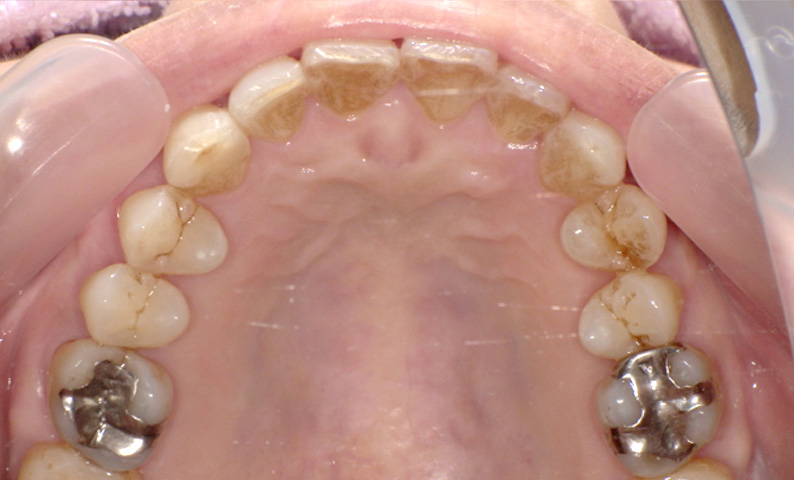

症例_004 「出っ歯」症例

治療期間:11ヶ月金額:30万円+税50代女性出っ歯八重歯上の前歯だけ

| Before | After |

|---|---|

症例_003 「出っ歯」症例

治療期間:7ヶ月金額:30万円+税20代女性出っ歯上の前歯だけ